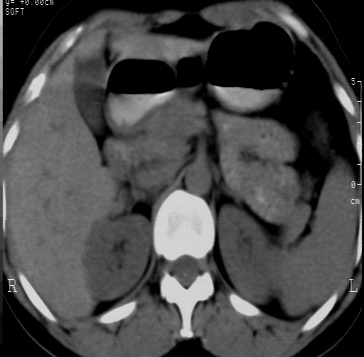

标题: CT24780:女 41岁 右肾多发低密度占位性病灶 [打印本页]

标题: CT24780:女 41岁 右肾多发低密度

女 41岁 超声检查:右肾多发实质性包块,性质待查(提示:错构瘤或其它病变),临床病史不详。

结果收到---右肾细胞癌;单就影像表现是应该首先考虑血管平滑肌脂肪瘤。